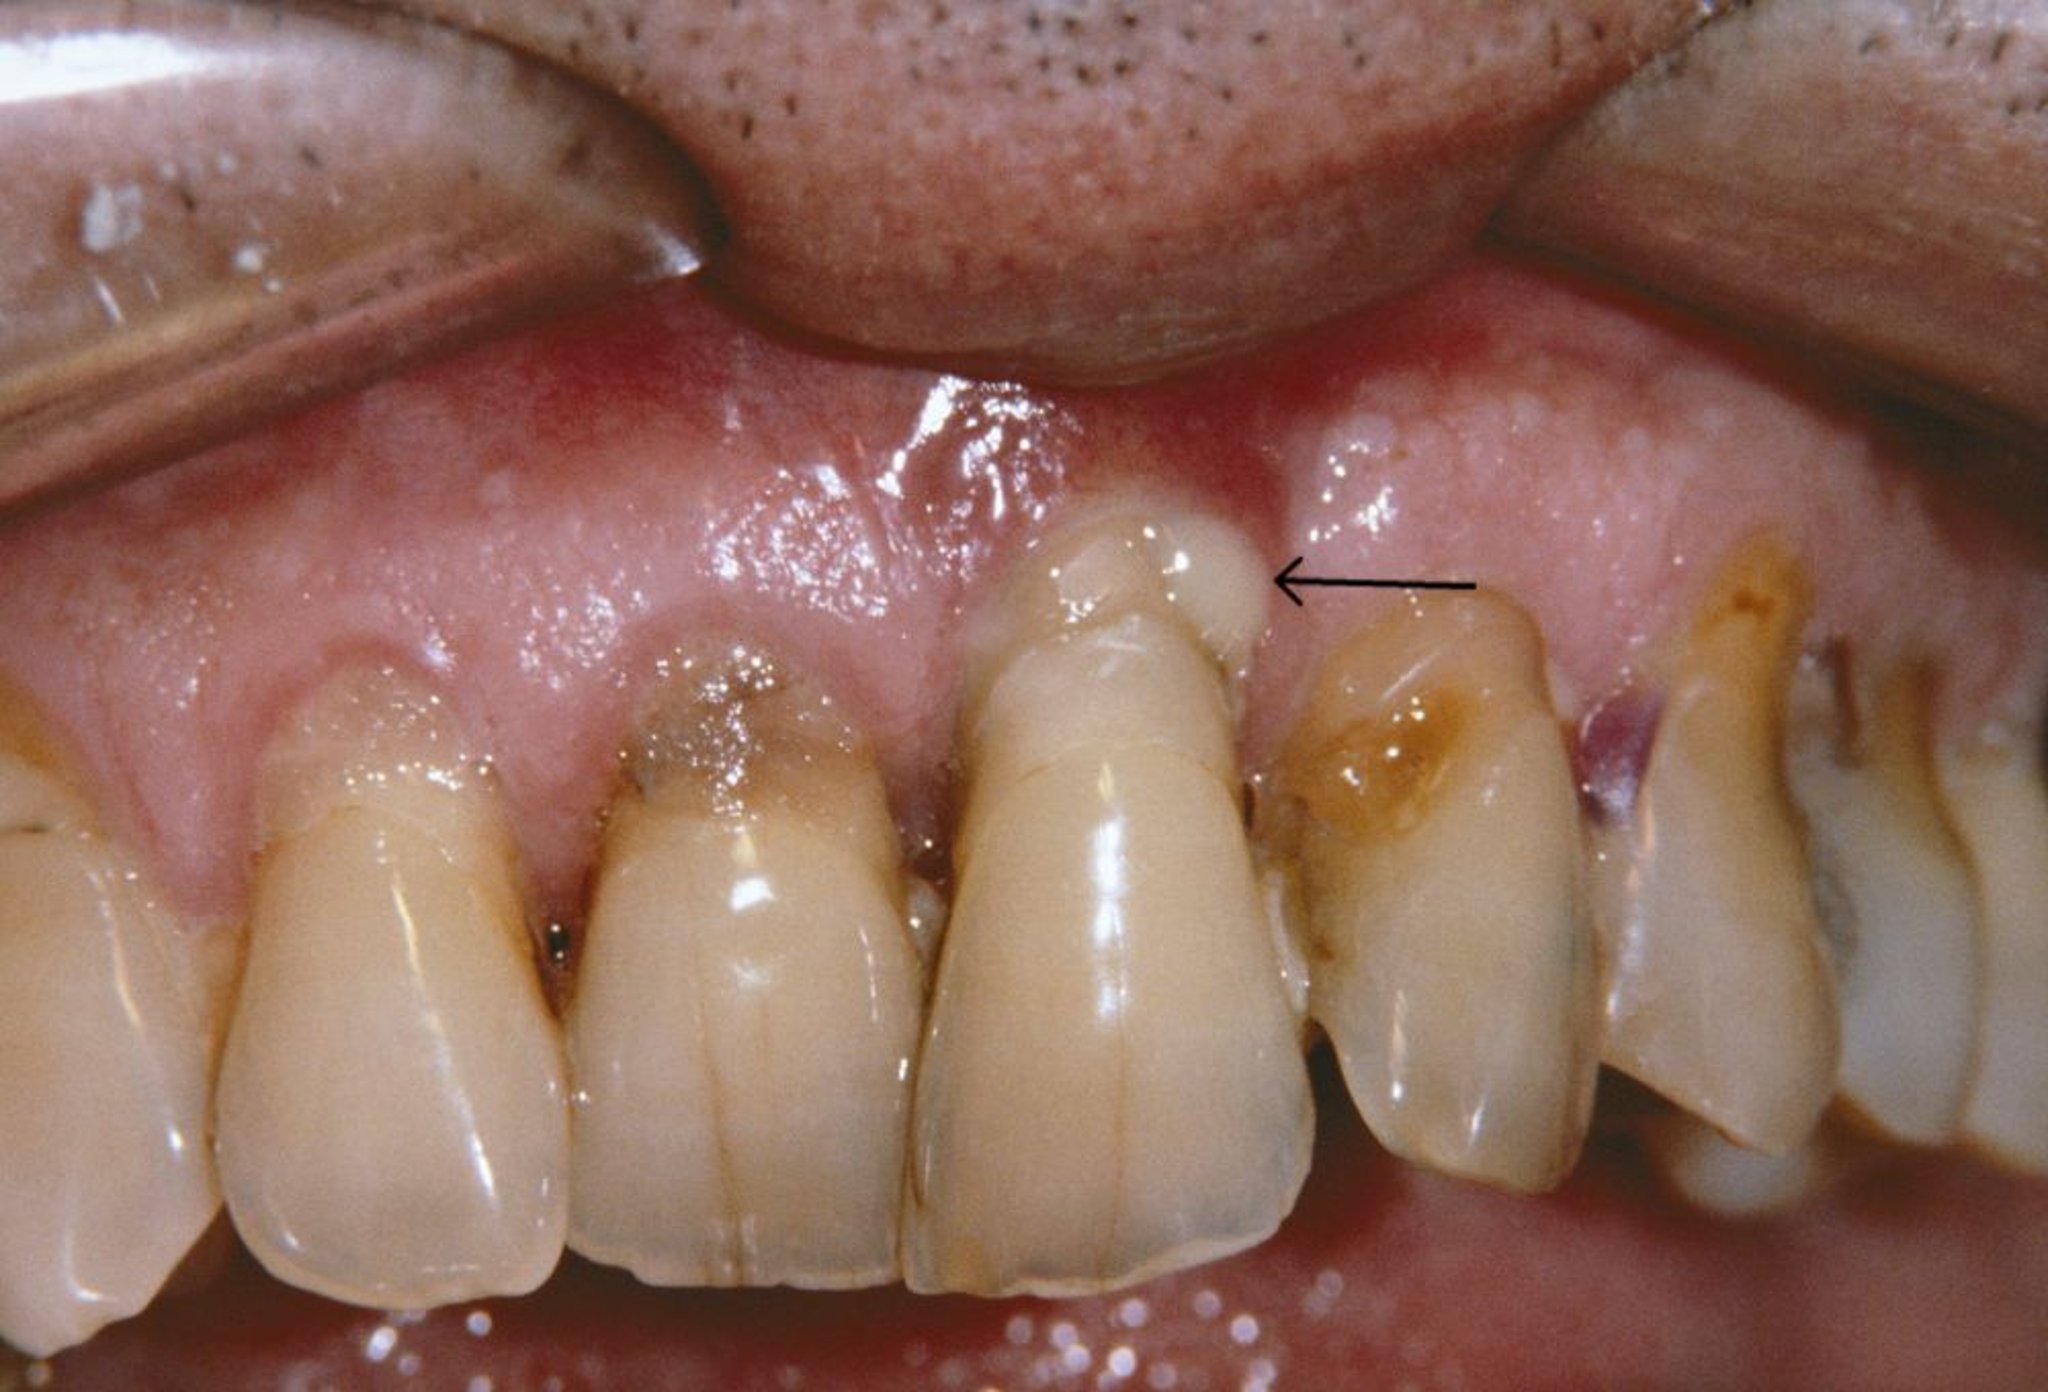

Ảnh này cho thấy nướu bị tụt và áp xe quanh răng (mũi tên) ở một người bị viêm quanh răng.